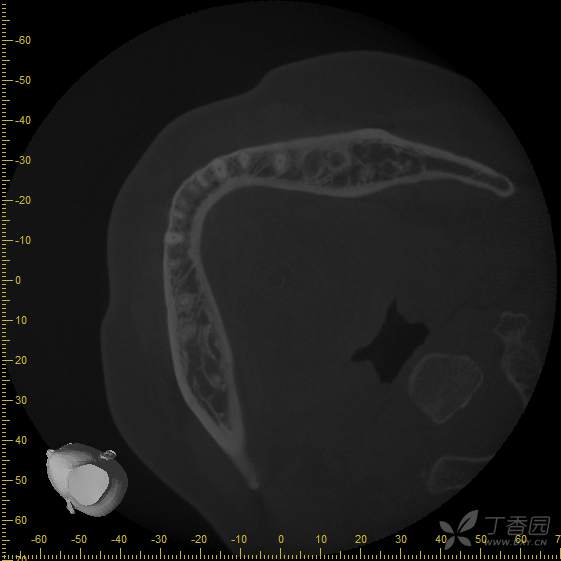

接诊时,36种植牙松1-2°,颊侧牙龈未见明显红肿。拍摄cbct后可见种植体周骨结合丧失,大量低密度影,骨吸收至根尖1/3,种植体浮出。